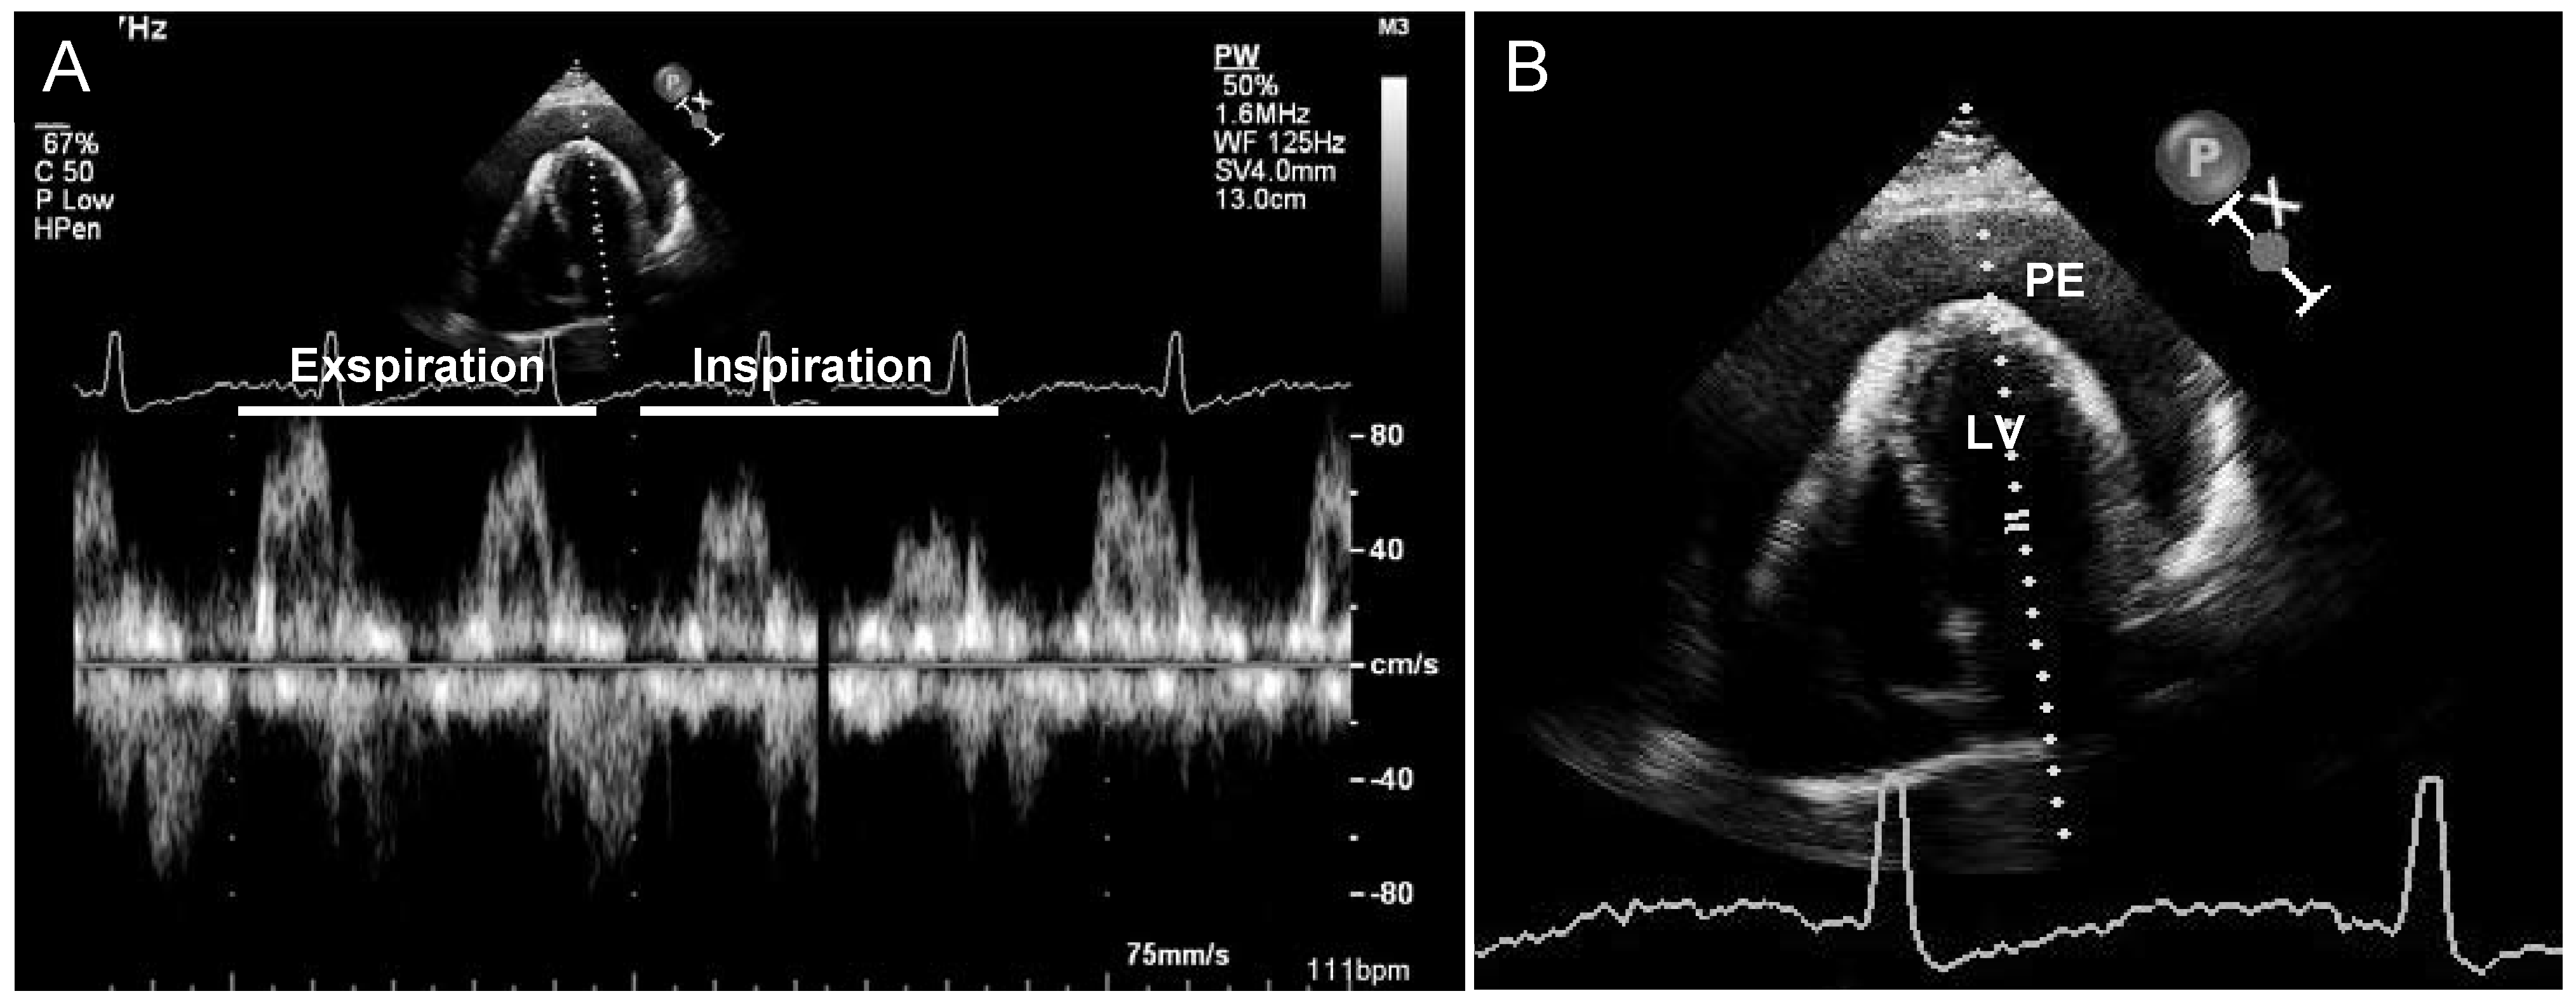

Abbildung 3. Transthorakale Echokardiographie. Nachweis eines zirkulären Perikardergusses mit maximaler Ausdehnung von 28 mm und atemvariabler Mitraleinstromkurve im PW-Doppler (A) als Zeichen der hämodynamischen Relevanz bei klinischen Zeichen einer Prätamponade. Vergrösserter Ausschnitt (B). PE = Perikarderguss; LV = linker Ventrikel.

Ein 31-jähriger, türkischstämmiger Patient stellte sich mit retrosternalem Druck und progredienter Dyspnoe auf unserer Notfallstation vor; aus der Vorgeschichte war ein unklarer, chronischer Perikarderguss bekannt, welcher bisher als nicht punktionswürdig betrachtet wurde. Im Status präsentierte sich ein tachykarder, normotensiver Patient, ein Pulsus paradoxus lag nicht vor. Die laborchemischen Untersuchungen waren bis auf eine leichte CRP-Erhöhung bland. Im Thoraxröntgen (Abb. 1) fand sich eine ausgeprägte Kardiomegalie mit kugelig konfigurierter Herzschattengrösse, elektrokardiographisch (Abb. 2) ein alternierender QRS-Ausschlag. Die Echokardiographie bestätigte einen eindrücklichen Perikarderguss (zirkulärer perikardialer Erguss von 2,5–3 cm, Abb. 3) mit Zeichen der Prätamponade. In der anschliessend durchgeführten Perikardiozentese konnten 1000 ml hämorrhagischer Erguss drainiert werden, worauf sich Symptomatik und Tachykardie des Patienten unmittelbar verbesserten. Die zytologische und bakteriologische Untersuchung blieb ohne Resultat, ein Quantiferon-Test war negativ. Anamnestisch und klinisch bestanden keine Hinweise für ein familiäres Mittelmeerfieber.